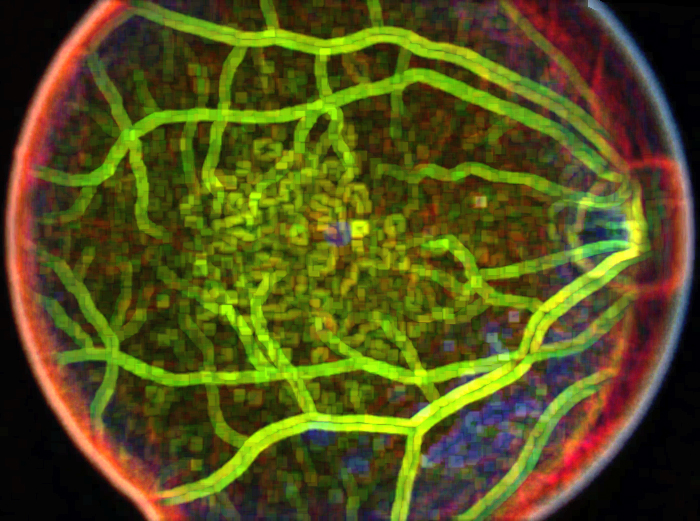

Retinal Metabolic Response to Cigarette Smoke

Retinal Metabolic Response to Cigarette Smoke